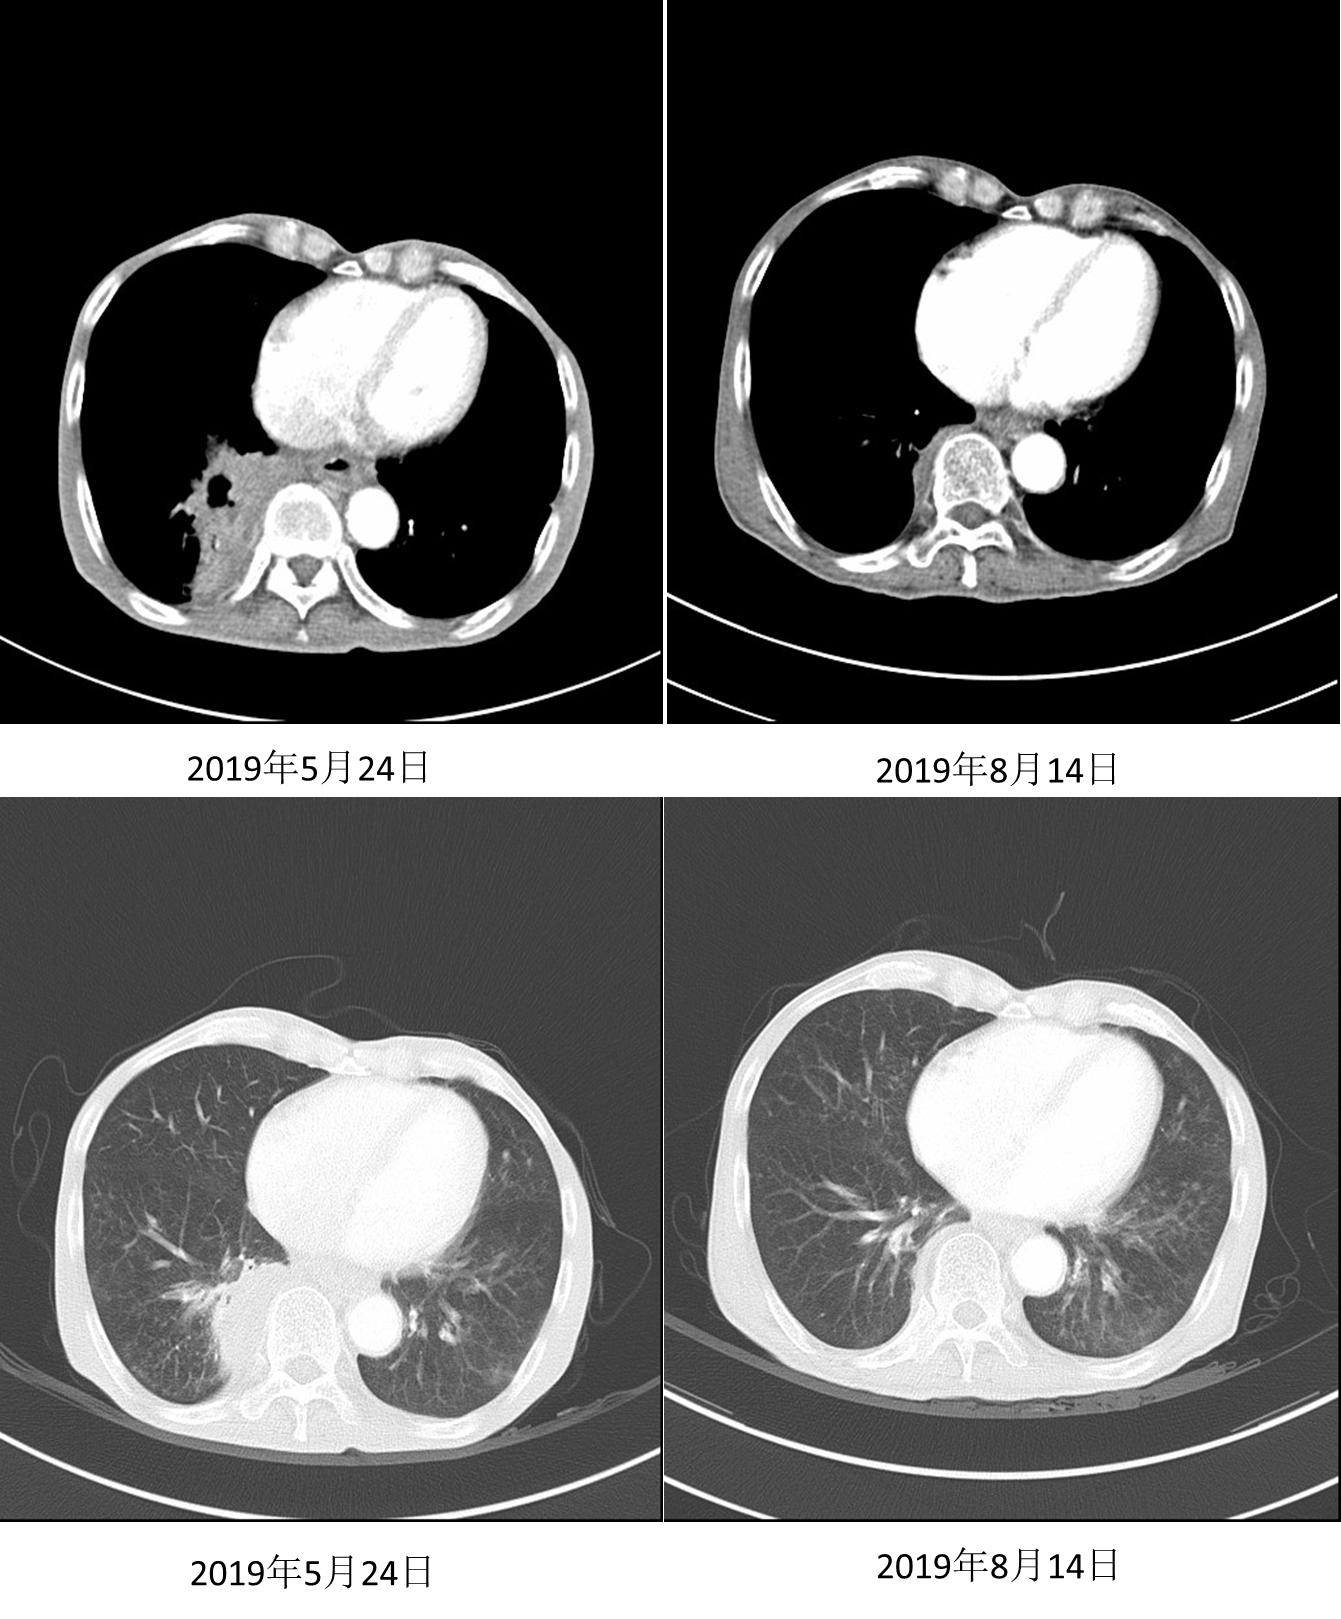

在沟通疗效和价格等因素后,患者自行选择信迪利单抗。2019年4月3日、4月30日、5月21日行信迪利单抗200mg D1治疗3个周期,患者症状缓解(自诉从“躺在床上”到“早上逛菜市场”)。2019年5月24日复查胸部CT示:右肺下叶软组织肿块影范围较前明显缩小,强化不均,范围约77mm *50mm。

图4. 2019年5月24日复查

2019年6月12日、7月2日继续行信迪利单抗200mg D1治疗2周期。2019年8月14日继续随访CT,结果示右肺下叶软组织肿块影范围较前明显缩小,强化不均,范围约28mm * 20mm,邻近胸膜增厚。疗效评价为部分缓解(PR),接近完全缓解(CR)。

图5. 2019年8月24日复查